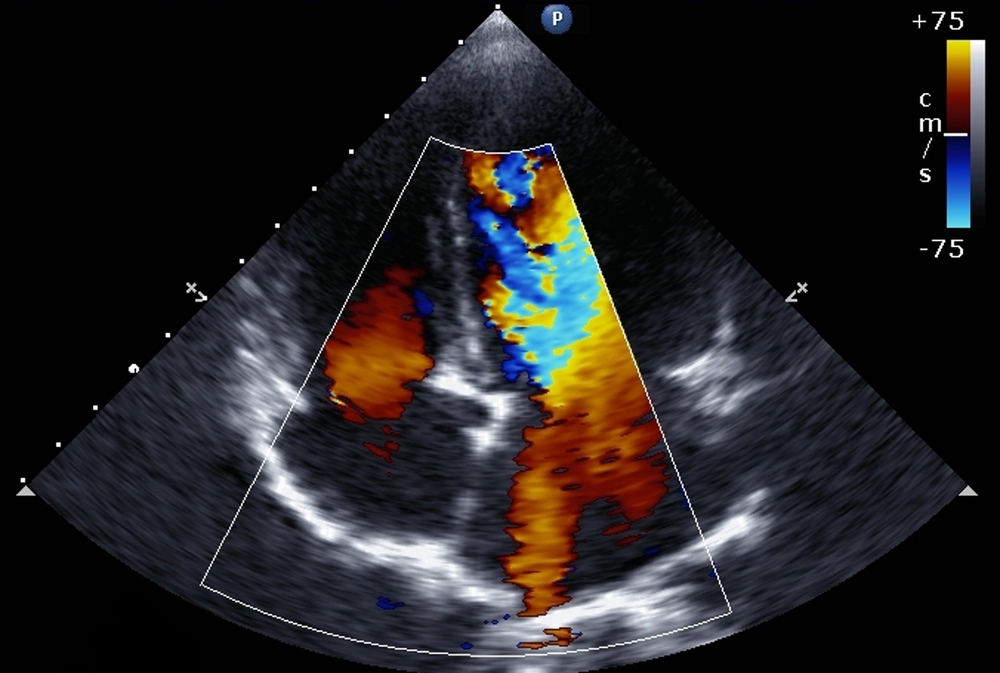

The heart’s right ventricle is the pump that pushes blood into the lungs to be oxygenated. Doctors have long known that problems affecting lung function, including inflammation triggered by respiratory viruses, can stress and impair this pump, usually by increasing the lungs’ resistance to blood flow. But the investigators believe the new study is the first to show that such an impairment is an independent predictor of COVID-19 mortality risk, with predictive value over and above that of other risk markers.

The median age of the patients was 64, and two-thirds were male. Dr. Kim and colleagues found that patients with a standard sign of right ventricle damage, the expansion or “dilation,” of the pumping chamber, were 1.43 times as likely to die during initial hospitalization for COVID-19. Patients whose right ventricles showed significantly below-normal contraction while pumping—a condition called “right ventricular dysfunction”—were nearly 3-fold as likely to die. These two heart signs were relatively common in the patients, being present in 35 percent and 15 percent, respectively.